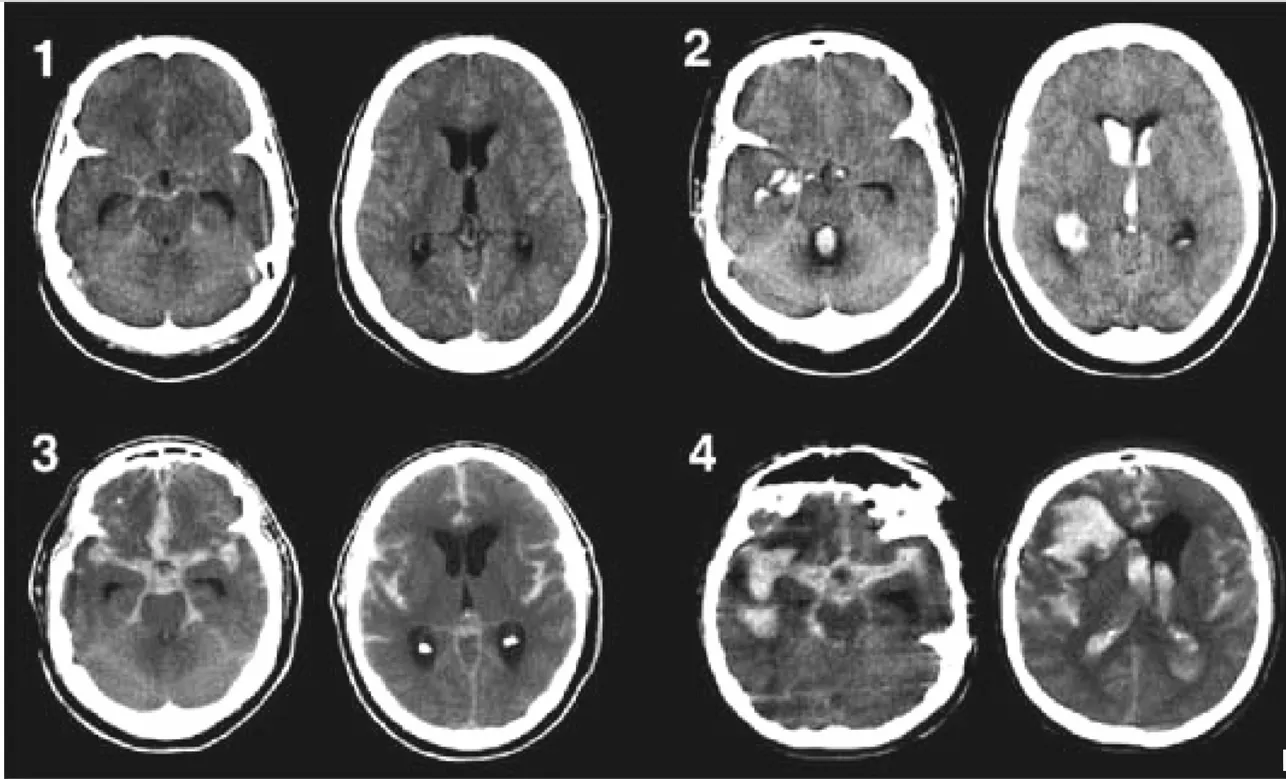

(해설) SAH의 정도를 나타내는 등급으로는 Fisher grading을 많이 사용합니다. 아래 표와 사진에 Fisher grading 의 각 단계별 정의와 예시가 있습니다.

(해설) 아래 사진은 정상 Basal cistern의 CSF density와 비교했을 때, SAH가 발생했을 경우, 시간에 따라 hemorrage의 density가 어떻게 변해가는 지 보여줍니다. 초기 사진인 1번에서는 basal cistern에 명확한 hyperdense lesion이 보이지만 subacute로 진행하면 (2) density가 떨어지기 시작하고, 좀 더 진행하면 (3) 더 어두워지기 때문에 항상 정상 basal cistern의 어두운 density가 잘 보이는지를 확인해야 합니다.